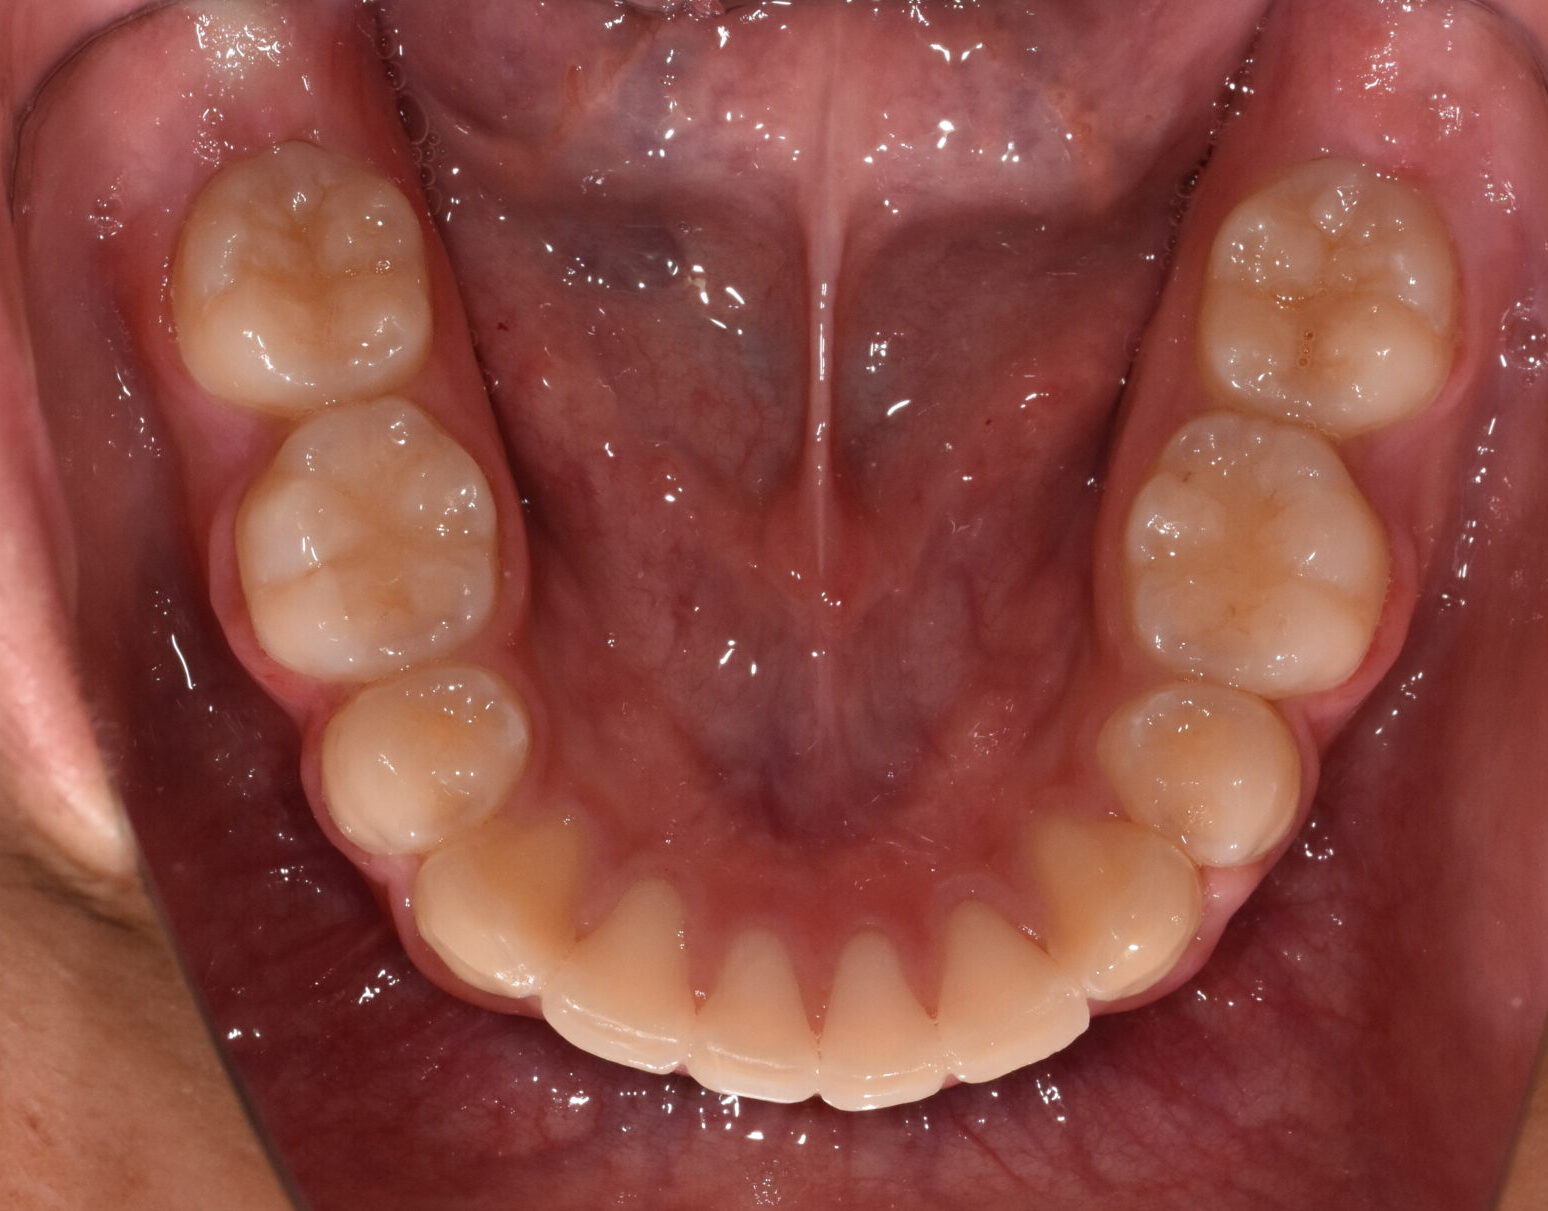

治療後

【診断】叢生、過蓋咬合

【治療方法】上下両側第一小臼歯抜歯、ワイヤー治療期間3年間、上顎口蓋にTPA(トランスパラタルアーチ)を行いました。